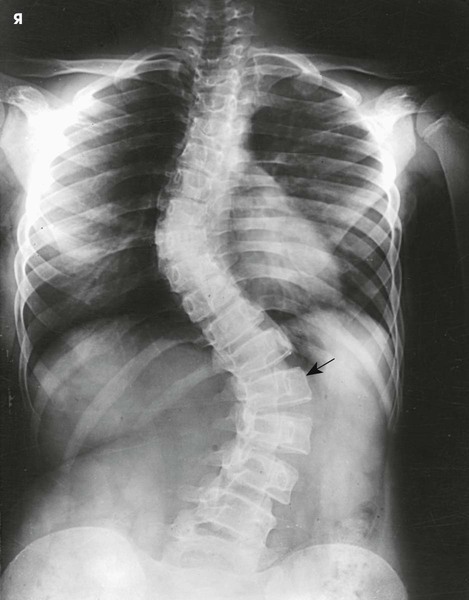

Scoliosis is an abnormal lateral curvature of the vertebral column with some associated rotation of the vertebral bodies at the curve. This condition may be caused by disease, surgery, or trauma, but it is frequently idiopathic. Scoliosis is commonly detected in the adolescent years. If not detected and treated, it may progress to the point of debilitation.

Diagnosis and monitoring of scoliosis requires a series of radiographs that may include upright, supine, and bending studies. A typical scoliosis study might include the following projections:

The PA (or AP) and lateral upright projections show the amount or degree of curvature that occurs with the force of gravity acting on the body (Fig. 8-131). Spinal fixation devices, such as Harrington rods, may also be evaluated. Bending studies are often used to differentiate between primary and compensatory curves. Primary curves do not change when the patient bends, whereas secondary curves do change with bending.